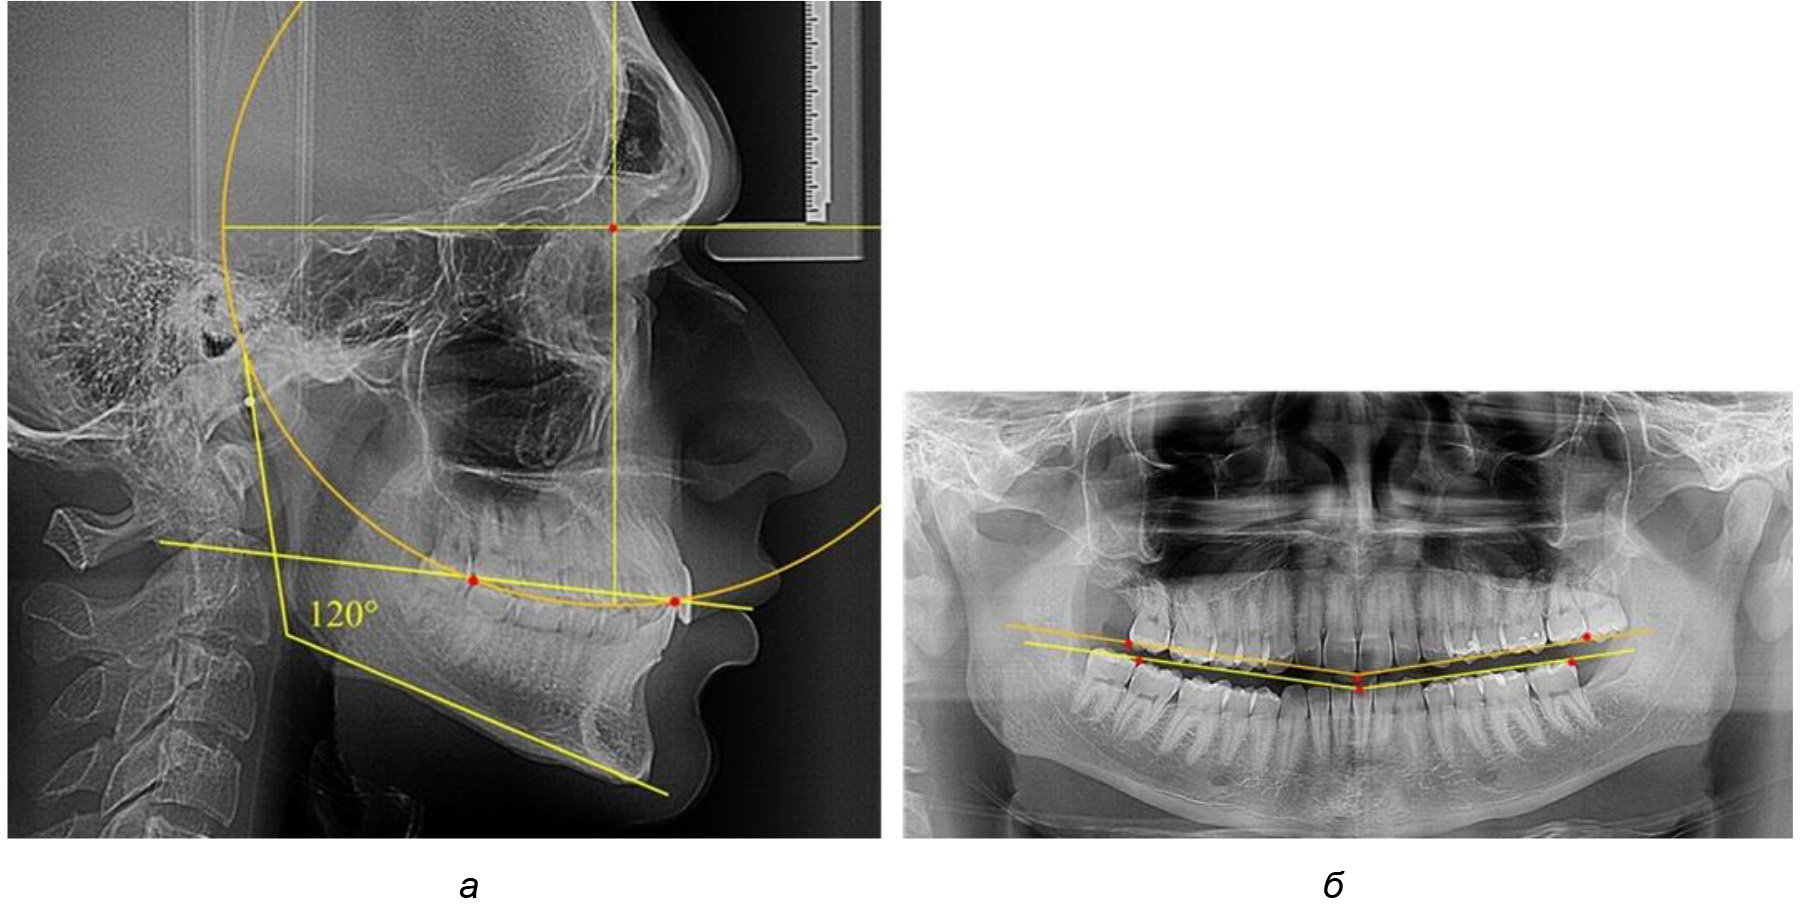

Таким образом, проведенное лечение техникой «прямой» дуги способствует нормализации окклюзионного равновесия и торку передних зубов, однако не соответствует оптимальному окклюзионному статусу, характеризующему физиологическую окклюзию. При этом величина нижнечелюстного угла оставалась на прежнем уровне (рис. 5).

Рис. 5. Особенности ТРГ при патологической кривой Spee до лечения (а) и после лечения (б) техникой «прямой» дуги

После лечения пациентов техникой «прямой» дуги, так же как и в 1-й подгруппе, было отмечено увеличение сагиттального размера окклюзионной лини в среднем на (2,38 ± 0,83) мм. Окклюзионная линия практически касалась окклюзионного контура всех жевательных зубов, и отмечалось практически полное отсутствие кривой Spee, так же как и у людей 1-й подгруппы 2-й группы (рис. 6).

Рис. 6. Особенности ТРГ при оптимальной кривой Spee до лечения (а) и после лечения (б) техникой «прямой» дуги

Таким образом, проведенное лечение техникой «прямой» дуги способствует нормализации окклюзионного равновесия и торку передних зубов, однако не соответствует оптимальному окклюзионному статусу, характеризующему физиологическую окклюзию. При этом величина нижнечелюстного угла оставалась на прежнем уровне.